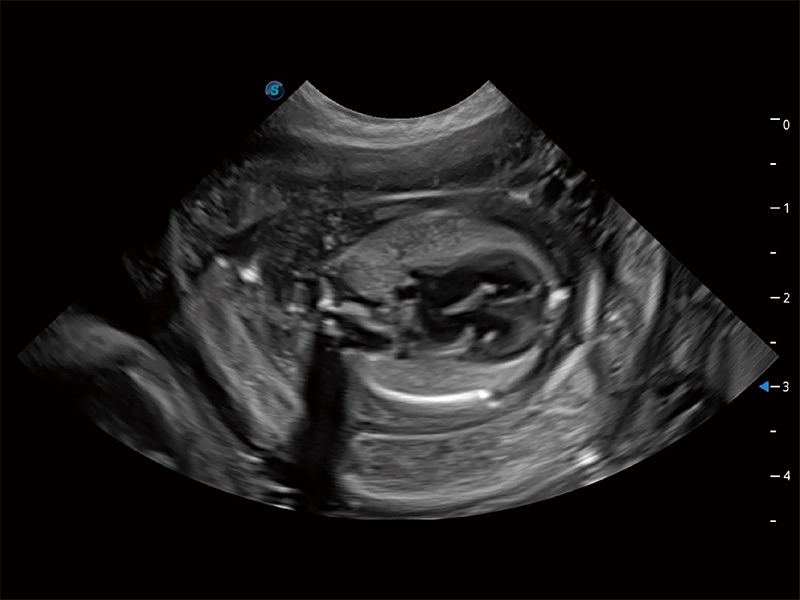

ProPet 80 专为动物医生设计,对不同的动物体型和生理结构作出了针对性的优化。通过动物影像专用软件,可满足个性化的应用需求,帮助动物医生获得更精确的诊断数据。

ProPet 80 全新的动物超声智能软件和丰富的探头群,为动物医生提供了高清晰度和精细分辨率的图像,无论在宠物、马科、畜牧还是实验室动物等应用中都可以轻松应对,为您的日常工作带来满意的体验。